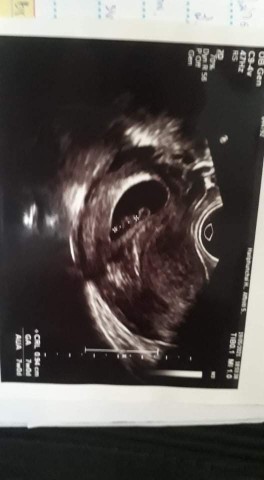

ภาพนี้ซาวน์ตอน 7week ค่ะแม่เห็นเป็นแบบนี้เเล้ว